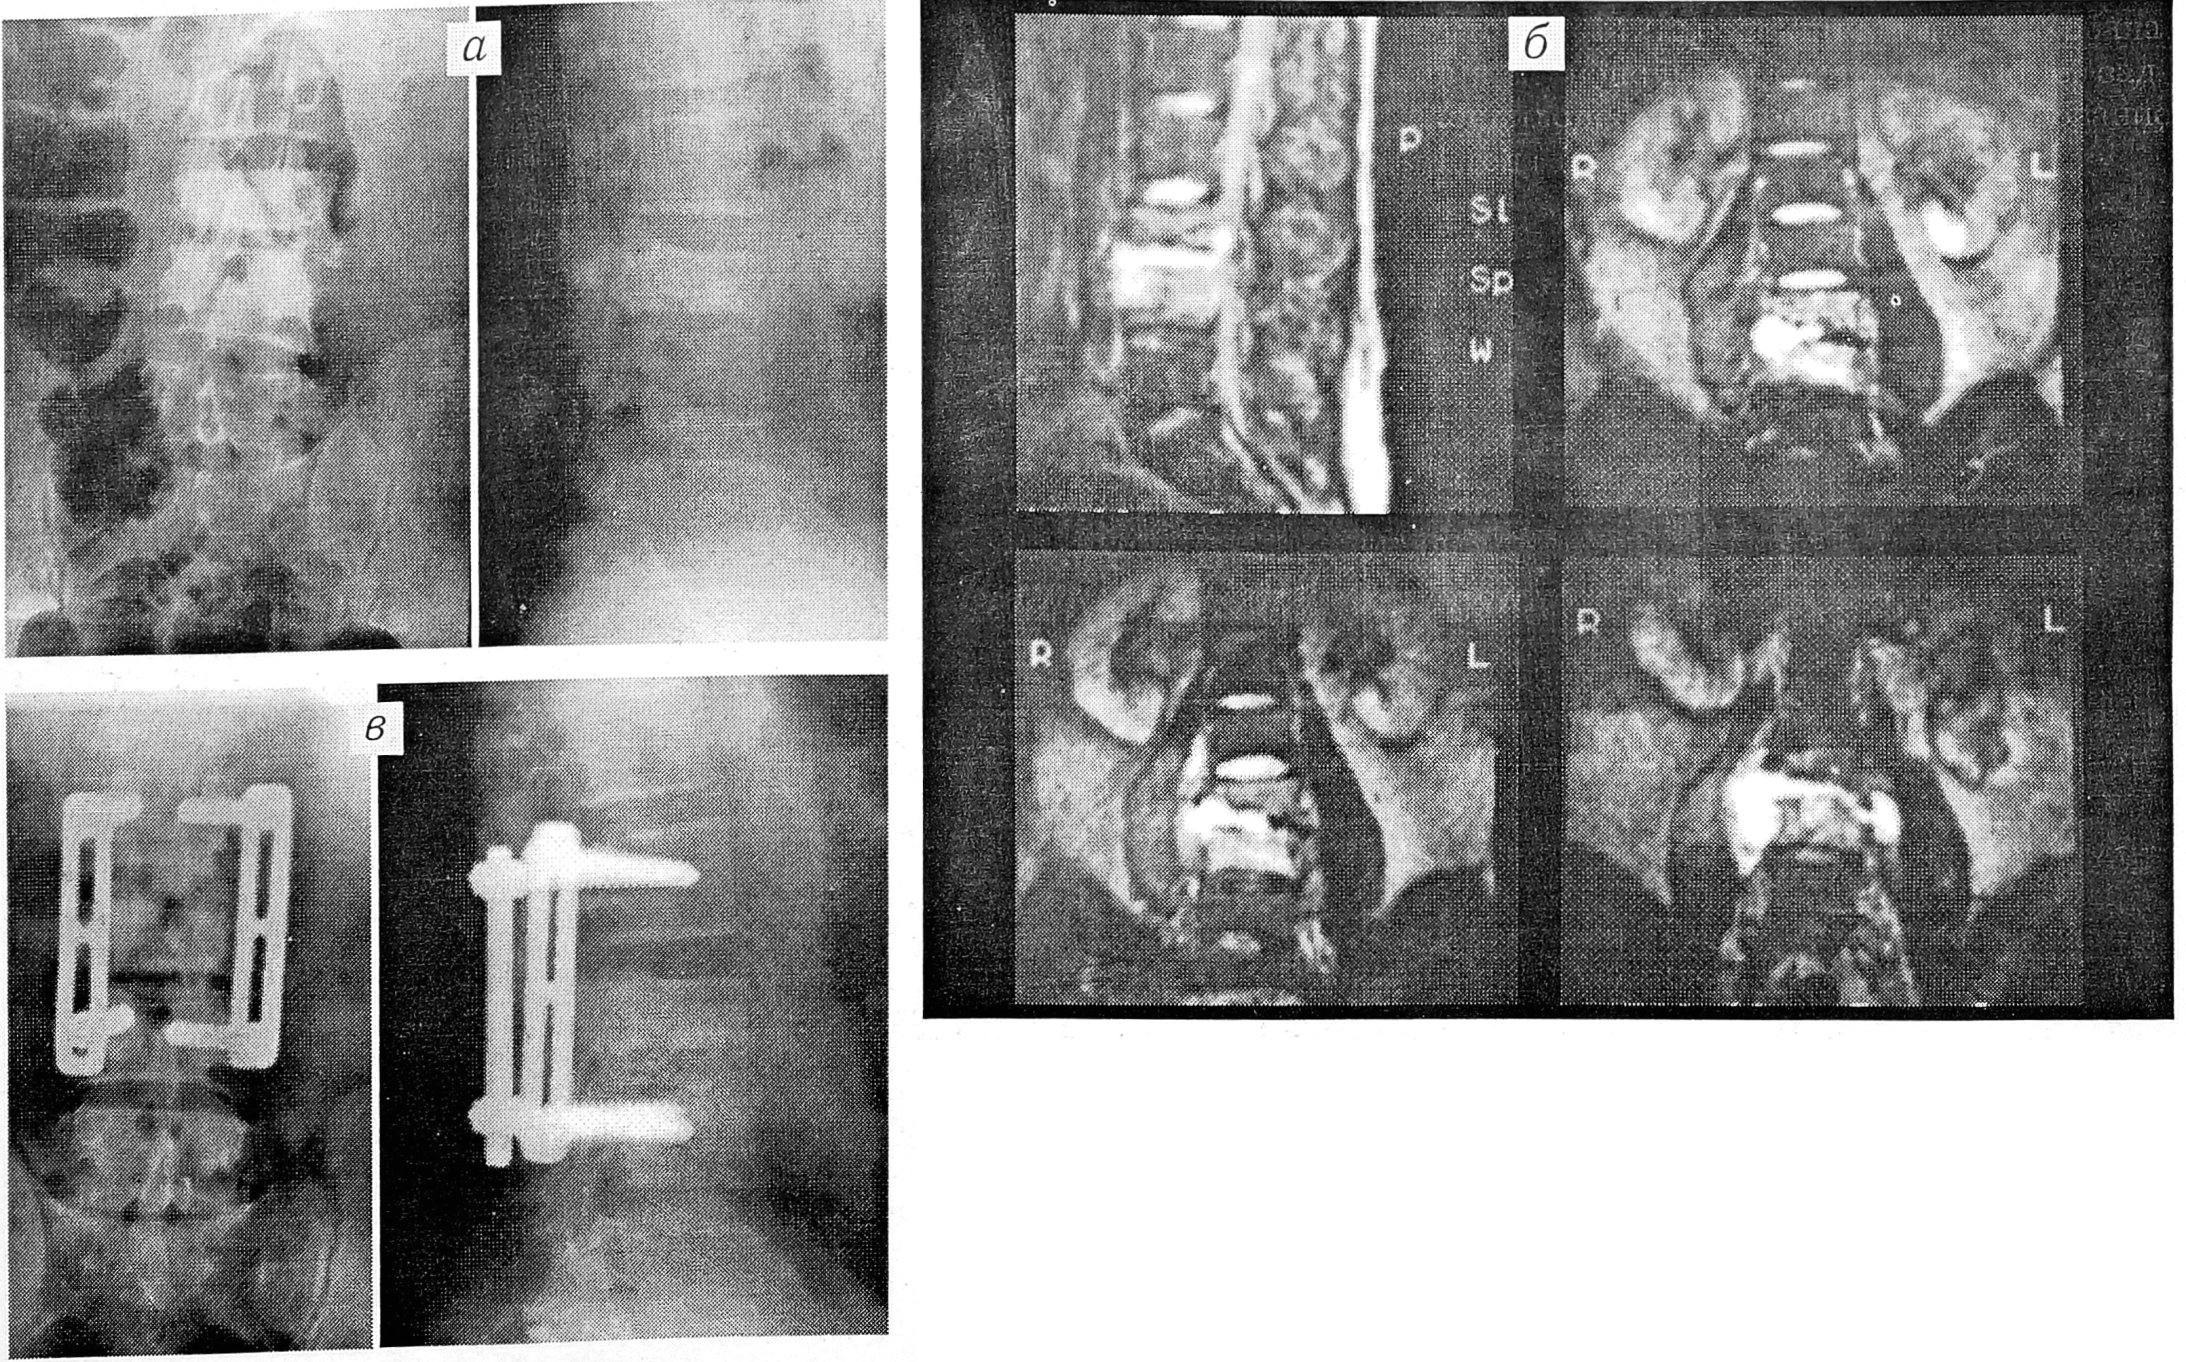

В одном случае транспедикулярная фиксация позвоночника была применена при туберкулезном поражении L3 позвонка (см. рис. 4).

Рис. 4. Больной Е.

С туберкулезным поражением L3 позвонка. На рентгенограммах до операции (а) видна деструкция тела L3 позвонка, на MP-томограмме (б), кроме того, определяется гнойный натечник. Операция (в): секвестрнекрэктомия L3 позвонка, санация гнойника, фиксация позвоночника системой Steffee, межтеловой спондилодез.

Тело этого позвонка было разрушено на 1/2 его высоты, при МР-томографии выявлен гнойный натечник, клинически отмечались сильное напряжение паравертебральных мышц, резкое ограничение движений в позвоночнике, выраженные боли в пояснице и в нижних конечностях, из-за которых больной не мог ходить.